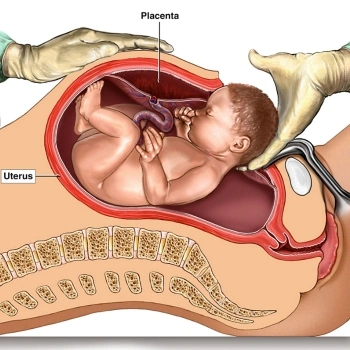

Is pregnancy care available for high-risk cases?

Absolutely, our experienced gynecologists specialize in managing high-risk pregnancies with advanced care and constant monitoring.